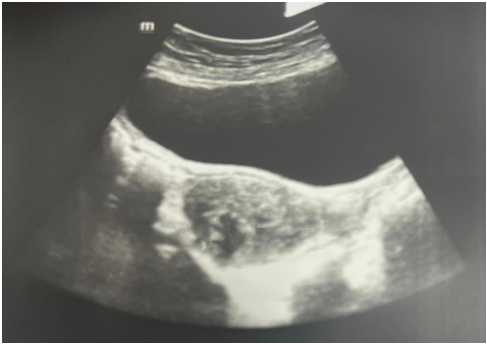

Pelvic ultrasound revealed a normal-sized uterus with small myomas (the largest measuring 24 x 18 mm, FIGO 3), as well as a left ovary increased in volume with heterogeneous echotexture, measuring 62 x 46 mm (Figure 1).

Figure 1: Ultrasound image showing an enlarged left ovary with heterogeneous echotexture, measuring 62x46 mm